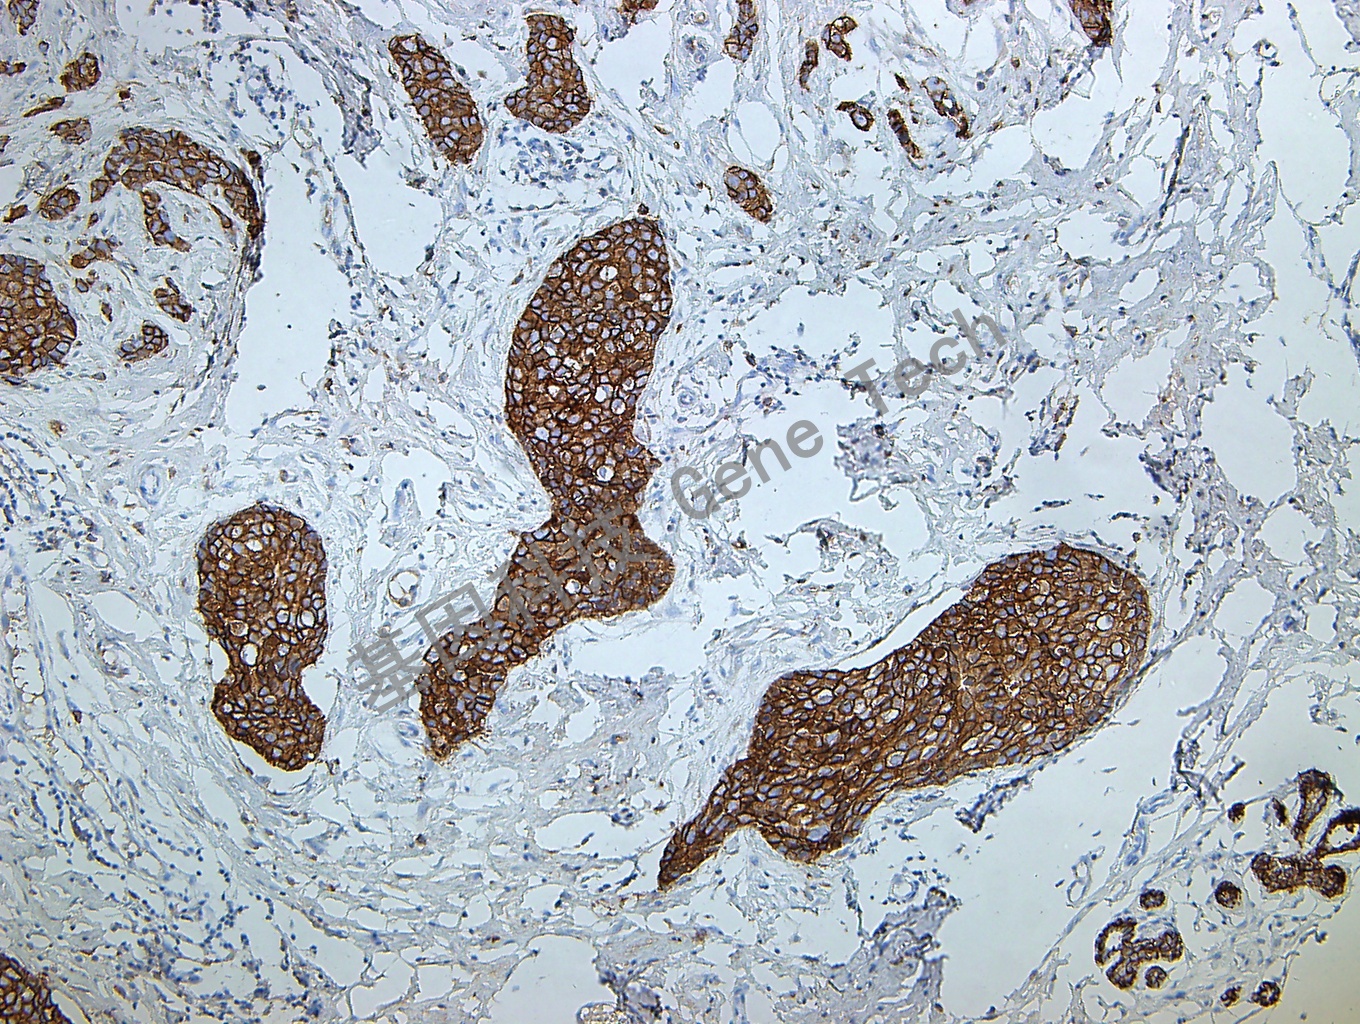

乳腺癌石蜡切片,用 E-Cadherin(GT2348)染色,细胞膜阳性,DAB 显色。

【阳性部位】细胞膜